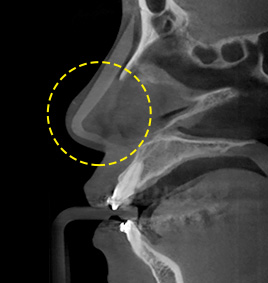

3D-CT nose surgery involves identifying not only the external parts of the nose but also symptoms and causes of nasal bone, crooked nose, nasal septal cartilage, nasal congestion, etc. As three-dimensional analysis using 3D-CT helps establish an adequate surgery plan and reduce damage to blood vessels and nerves, safe and precise operation can be performed.

3D-CT analyzes the nose three-dimensionally.

FACE uses advanced 3D-CT equipment to analyze the overall condition of nasal bone, nasal septal cartilage, skin tissue, asymmetry, etc.,

which cannot be identified by general consultation,

in order to secure safer and more precise nose surgery.